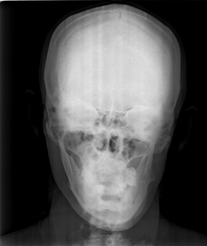

Radiographic limbs show bony ankylosis of the elbow joint, with associated hypoplasia of the ulna and proximal radius, leading to elbow flexion deformity on the left side (Figure 5). Chest x-rays show no apparent abnormalities: normal lung fields, cardiac silhouette, and bony structures (Figure 6) PA skull view show hypoplastic maxilla, prominent antigoinial notch and deviation of mandible to left side (Figure 7 &Table 1).

Figure 7 Posteroanterior skull view revealing hypoplastic maxilla, prominent antegonial notch, and mandibular deviation to the left side.